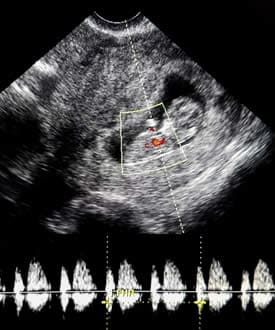

Come neuroscienziata e madre di due bambini, ho sempre voluto sapere come funziona il cervello dei più piccoli. Secondo alcuni siti web che avevo letto, l’attività elettrica era stata registrata dal cervello di un feto umano solo sei settimane e tre giorni dopo il concepimento (1). Sarebbe solo tre settimane dopo che il cuore fetale inizia a battere (2) e una settimana dopo i primi movimenti fetali registrati (3). Ma, come vi dirà qualsiasi neuroscienziato, è difficile registrare l’attività elettrica dal cervello umano adulto utilizzando l’elettroencefalografia (EEG) a causa dell’interferenza dei muscoli del cuoio capelluto e delle ossa craniche. Come potrebbe un bambino delle dimensioni di un acino produrre abbastanza attività elettrica da essere rilevato?

Per trovare la risposta, ho dovuto visitare la Biblioteca del Congresso e rispolverare un articolo scientifico così vecchio da non essere disponibile pubblicamente su Internet. Il documento ha dettagliato la ricerca sul cervello che ha avuto luogo durante le tragiche emergenze mediche a Filadelfia negli anni ’50. Nel 1955, Winslow Borkowski e Richard Bernstine, medici del Jefferson Medical College Hospital, preservarono temporaneamente un piccolo bambino non ancora nato rimosso 45 giorni dopo il concepimento durante una gravidanza extrauterina e registrato dalle aree frontale e occipitale del suo cervello. Il team ha utilizzato elettrodi ad ago per registrare l’attività cerebrale a 3 millimetri e 1 centimetro sotto la superficie del cervello (4). Questi elettrodi sono penetrati nel tessuto cranico, il che risolve il problema dell’interferenza elettrica dai muscoli vicini. A 45 giorni dal concepimento, il cervello è piegato in avanti ed è grande quasi quanto l’intero corpo del feto, consentendo queste registrazioni profonde (5).

I medici hanno iniziato a registrare dal feto di 45 giorni 10 minuti dopo l’intervento che lo ha separato dall’afflusso di sangue materno e hanno continuato a registrare per quasi 90 minuti fino alla morte cerebrale completa, determinata dalla completa mancanza di attività EEG (4). Sebbene possa essere sorprendente che l’attività cerebrale del feto sia continuata per così tanto tempo dopo la separazione dal flusso sanguigno ossigenato di sua madre, i neuroni neonatali hanno meccanismi protettivi per aiutarli a sopravvivere al disagio metabolico e agli ambienti a basso contenuto di ossigeno (7).

Gli elettroencefalogrammi (EEG) registrano l’attività elettrica spontanea generata dai neuroni attivi nel cervello. In generale, il cervello produce attività elettrica divisa in due parti: componenti ritmiche simultanee, spesso chiamate onde cerebrali, e potenziali correlati agli eventi, legati alla stimolazione sensoriale o al pensiero correlato al compito. Gli scienziati che osservano un EEG non possono dire ciò che una persona sta pensando e sentendo, ma i potenziali relativi agli eventi mostrano che il cervello sta percependo e percependo il suo ambiente. I potenziali di evento sono anche facili da rilevare dal cuoio capelluto o, nel caso di un nascituro, dagli elettrodi sulla superficie della pancia della madre. Da misurazioni esterne, sappiamo che un feto di 26 settimane dopo il concepimento risponde ai suoni con potenziali correlati all’evento (8), ma limitazioni tecniche impediscono ai ricercatori di ottenere dati chiari in età gestazionali precedenti.